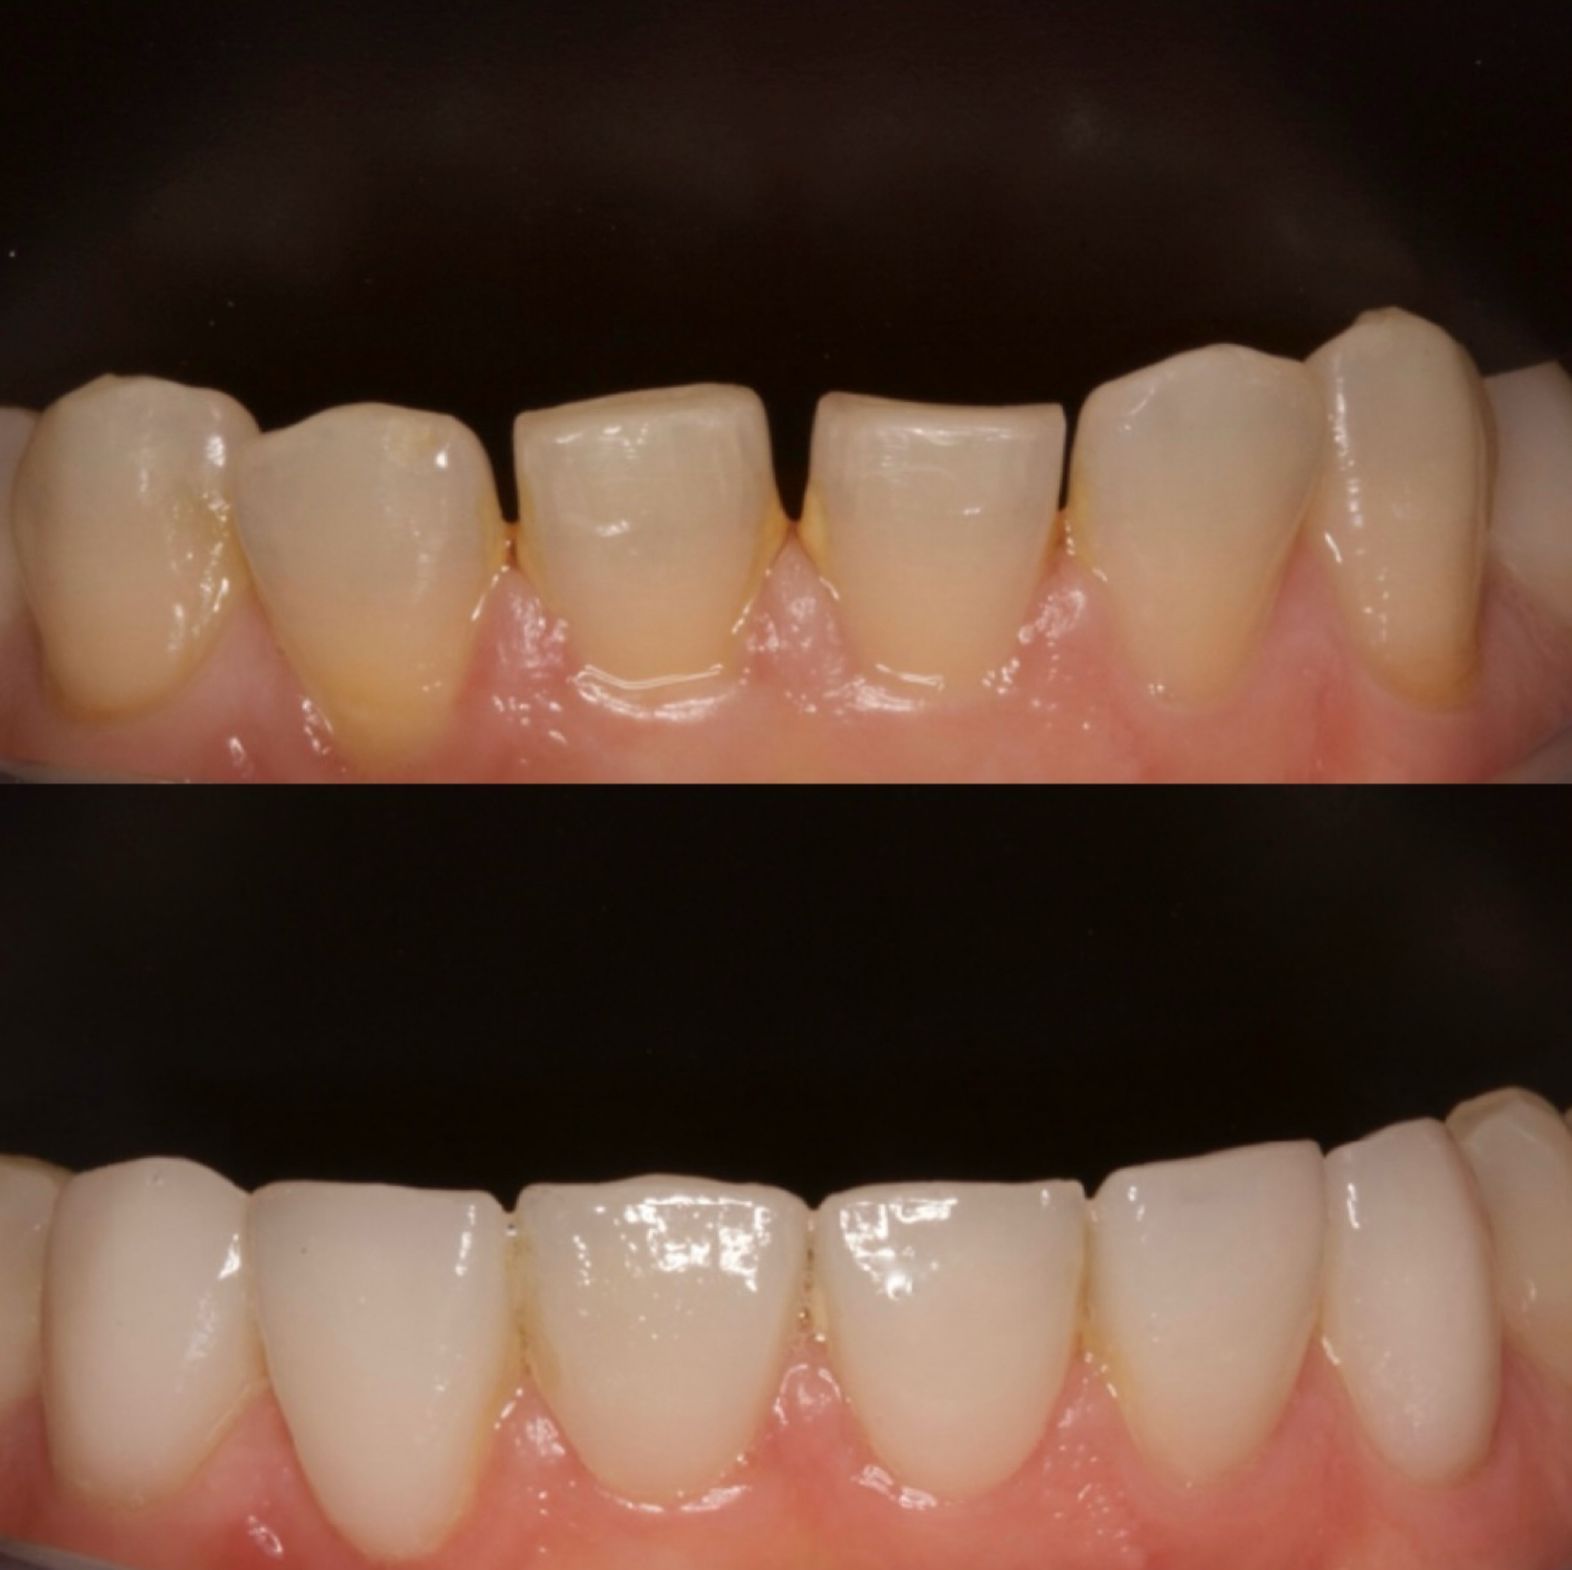

CARILLAS COMPOSITE FRENTE ANTERIOR

CARILLAS DE PORCELANA SUPERIORES

CARILLAS DE PORCELANA INFERIORES

CARILLAS DE PORCELANA TRATAMIENTO FINALIZADO